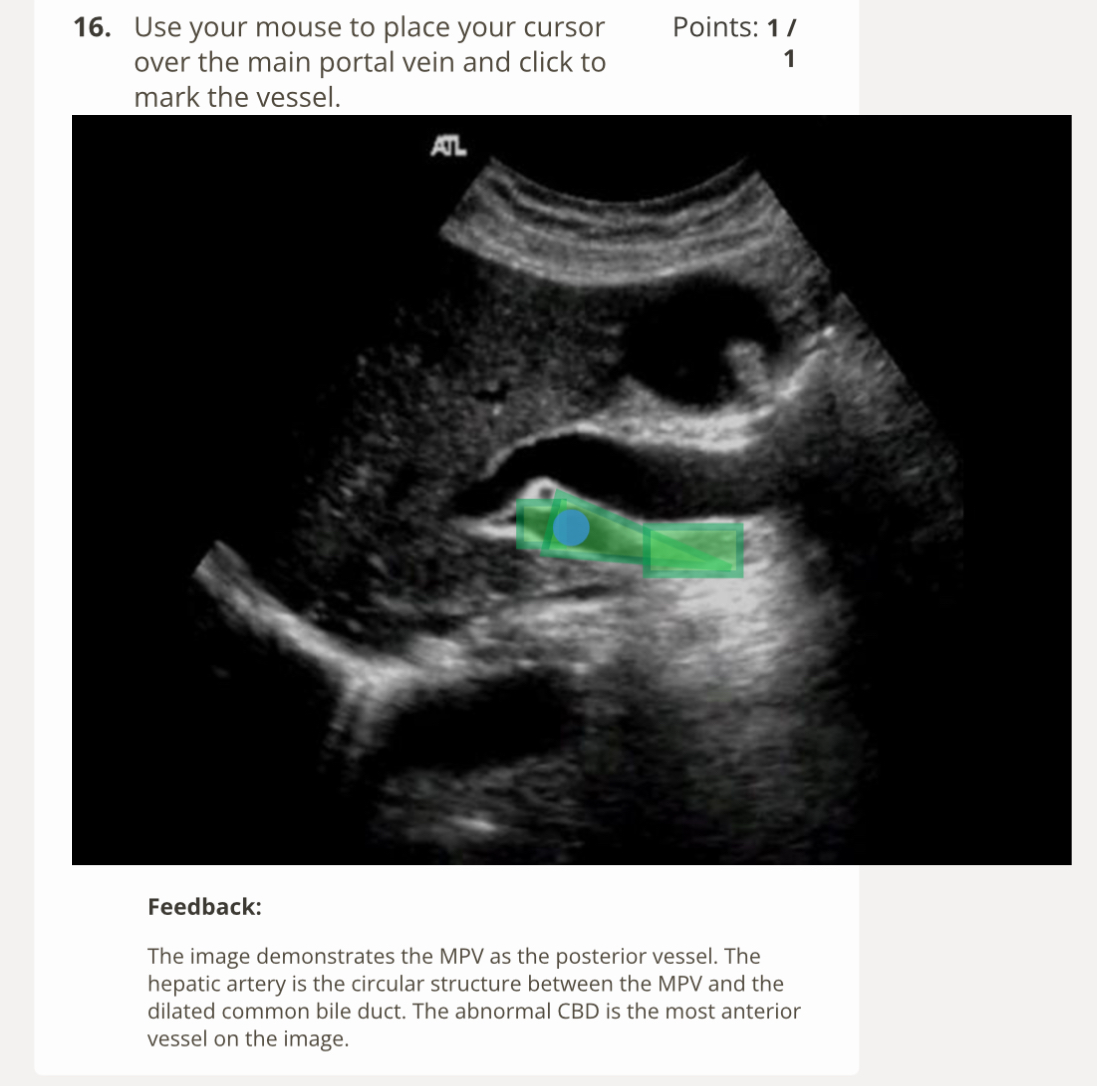

Diaphragm sign- when using an abdominal approach to view the fluid, fluid below the diaphragm and more centrally located = ascites; fluid above the diaphragm and more peripherally located= pleural effusion.

Displaced crus sign- if the fluid is displacing the crus a way from the spine, it is located on the chest cavity

Bare area sign- pleural fluid will extend behind the liver at the level of the bare are a, ascites cannot reach this area